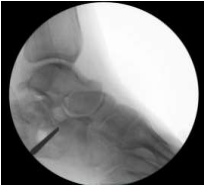

Postoperative Care and Optimizing Recovery and Monitoring Outcomes

Following the minimally invasive procedure, the patient's care focused on optimizing recovery and preventing potential complications. Thromboembolic prophylaxis with anticoagulants was resumed 12 hours postoperatively, Patient did not require much pain control and he was discharged home on the first postoperative day. Strict non-weight bearing on the left lower limb was enforced for the initial two weeks to allow for undisturbed fracture healing and soft tissue recovery. Regular follow-up appointments were scheduled within the orthopedic foot and ankle clinic to monitor progress and address any emerging concerns. Thromboembolic prophylaxis with Enoxaparin (40 mg once daily subcutaneously) was continued for two weeks following discharge. The dressing clinic visit within the first week confirmed no signs of infection or complications. Suture removal was performed at the two-week mark, revealing a well-healed wound with no soft tissue issues. After the initial non-weight bearing period, the patient progressed to partial weight bearing for gradual return to mobility. Follow-up radiographs (Figures 15, 16, and 17) were obtained to assess fracture alignment and stability. Additionally, a CT scan was performed within three weeks postoperatively (Figures 18, 19, 20, and 21) for in-depth evaluation of the internal components and fracture healing process. The crucial angle of Gissane on the follow-up CT scan measured approximately 145 degrees (Figure 22), indicating near-anatomical restoration of the posterior facet and a significant improvement from the initial measurements. Overall, the patient's postoperative course was uneventful, with no reported complications or concerns. Continued follow-up appointments and imaging at scheduled intervals will be crucial to monitor long-term fracture healing, maintain optimal outcomes, and address any potential issues that may arise.